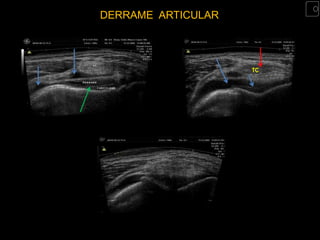

DERRAME E/OU BURSITE SUPRA-PATELAR

•   Qualquer aumento da quantidade de

líquido no recesso suprapatelar é anormal.

•   Uma compressão firme no recesso

suprapatelar desplaza o líquido para o

espaço articular e permite medir a

espessura da sinovial, e o Doppler color

indicará a presença de processo

inflamatorio ativo

DERRAME ARTICULAR

TC